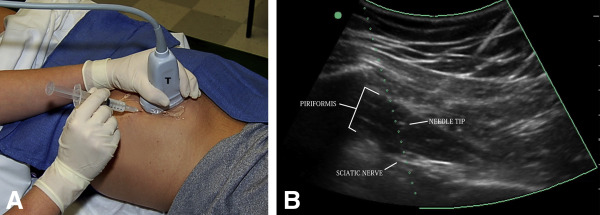

٣- الابر الكرتزونيه تحت الاشعه فوق الصوتيه او السينيه ( كما هو موضح في الصوره )